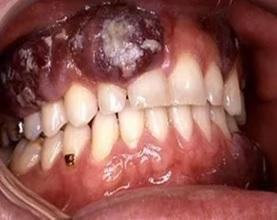

Так выглядит рак на слизистой верхней челюсти.

После масштабного исследования влияния снюса на организм в 1992 году его продажу запретили в странах ЕС. Бездымный табак серьезно влияет на цитологические изменения эпителия слизистой оболочки полости рта практически у четверти исследованных. На клеточном уровне были выявлены признаки воспаления и повреждения слизистой полости рта (лейкоплакии), которое может усугубляться при наличии канцерогенных факторов и вредных привычек. А длительное воздействие снюса может привести и к развитию опухолевой патологии слизистой оболочки полости рта.

Лейкоплакия является наиболее распространенной из потенциально злокачественных поражений слизистой оболочки полости рта и встречается примерно в шесть раз чаще у лиц, употребляющих жевательный табак, чем у некурящих.